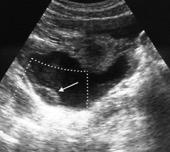

Signos radiológicos TC

Hallifax RJ et al. State-of-the-art: Radiological investigation of pleural disease Respiratory Medicine 2017

Nivel hidroaéreo o burbujas

Forma lenticular o elíptica Ángulos obtusos

> Grasa Extrapleural (60-80%)

Situación no gravitacional (no siempre)

Compresión de estructuras pulmonares

Límite muy bien definido Tabicación